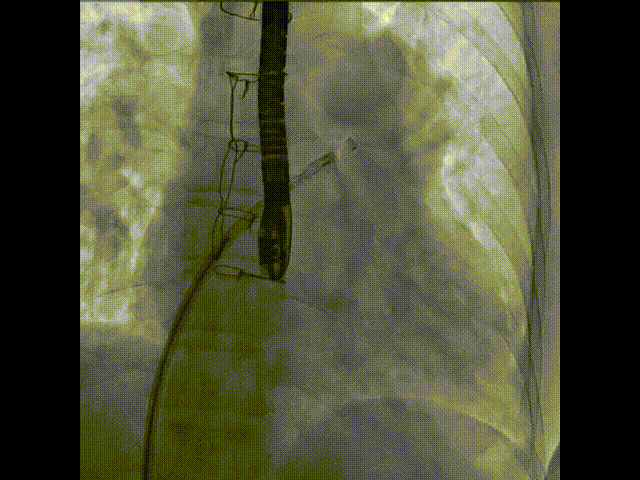

術中首先在局麻下穿刺股動脈、股靜脈,完成心導管檢查評估后轉為全麻,在食道超聲引導下穿刺房間隔,穿刺成功后將加硬導絲送入左上肺靜脈建立軌道,根據(jù)患者病情行球囊預擴張后植入6mm孔徑房間隔造孔支架,經(jīng)透視及食道超聲評估支架左右盤展開良好,夾持于房間隔兩側,固定穩(wěn)定、位置良好,食道彩超顯示房水平右向左為主分流,分流孔直徑符合預期大小,心導管檢查評估達到預期效果,釋放造孔支架。術后12h患者下床活動,恢復順利,擬于近日完善術后評估后出院。